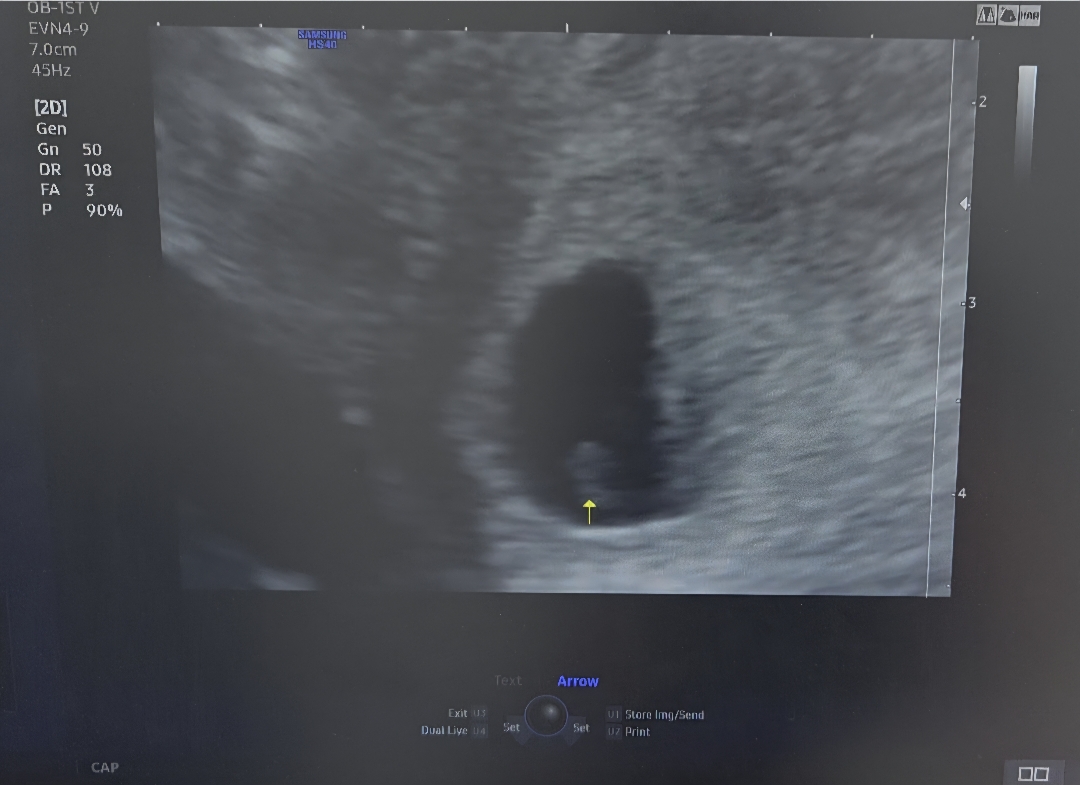

6주 2일차 초음파로 아기난황 보고왔어요..

난황이라고 보여주는건 흐릿하게 보이고 표시된 부분이 아기가 될거라는데 이정도면 잘크고있는거겠죠?ㅠㅠ 난황이 제 눈에는 잘 안보이긴했는데 별말 없으시긴했어요ㅠㅠ 마지막생리시작일 기준보다 5일정도 예정일을 빠르게 보시긴 하셨는데 심장소리를 못들어서인가 마음이 놓이질 않네요ㅠㅠ 다들 이런거겠죠?ㅠㅠ